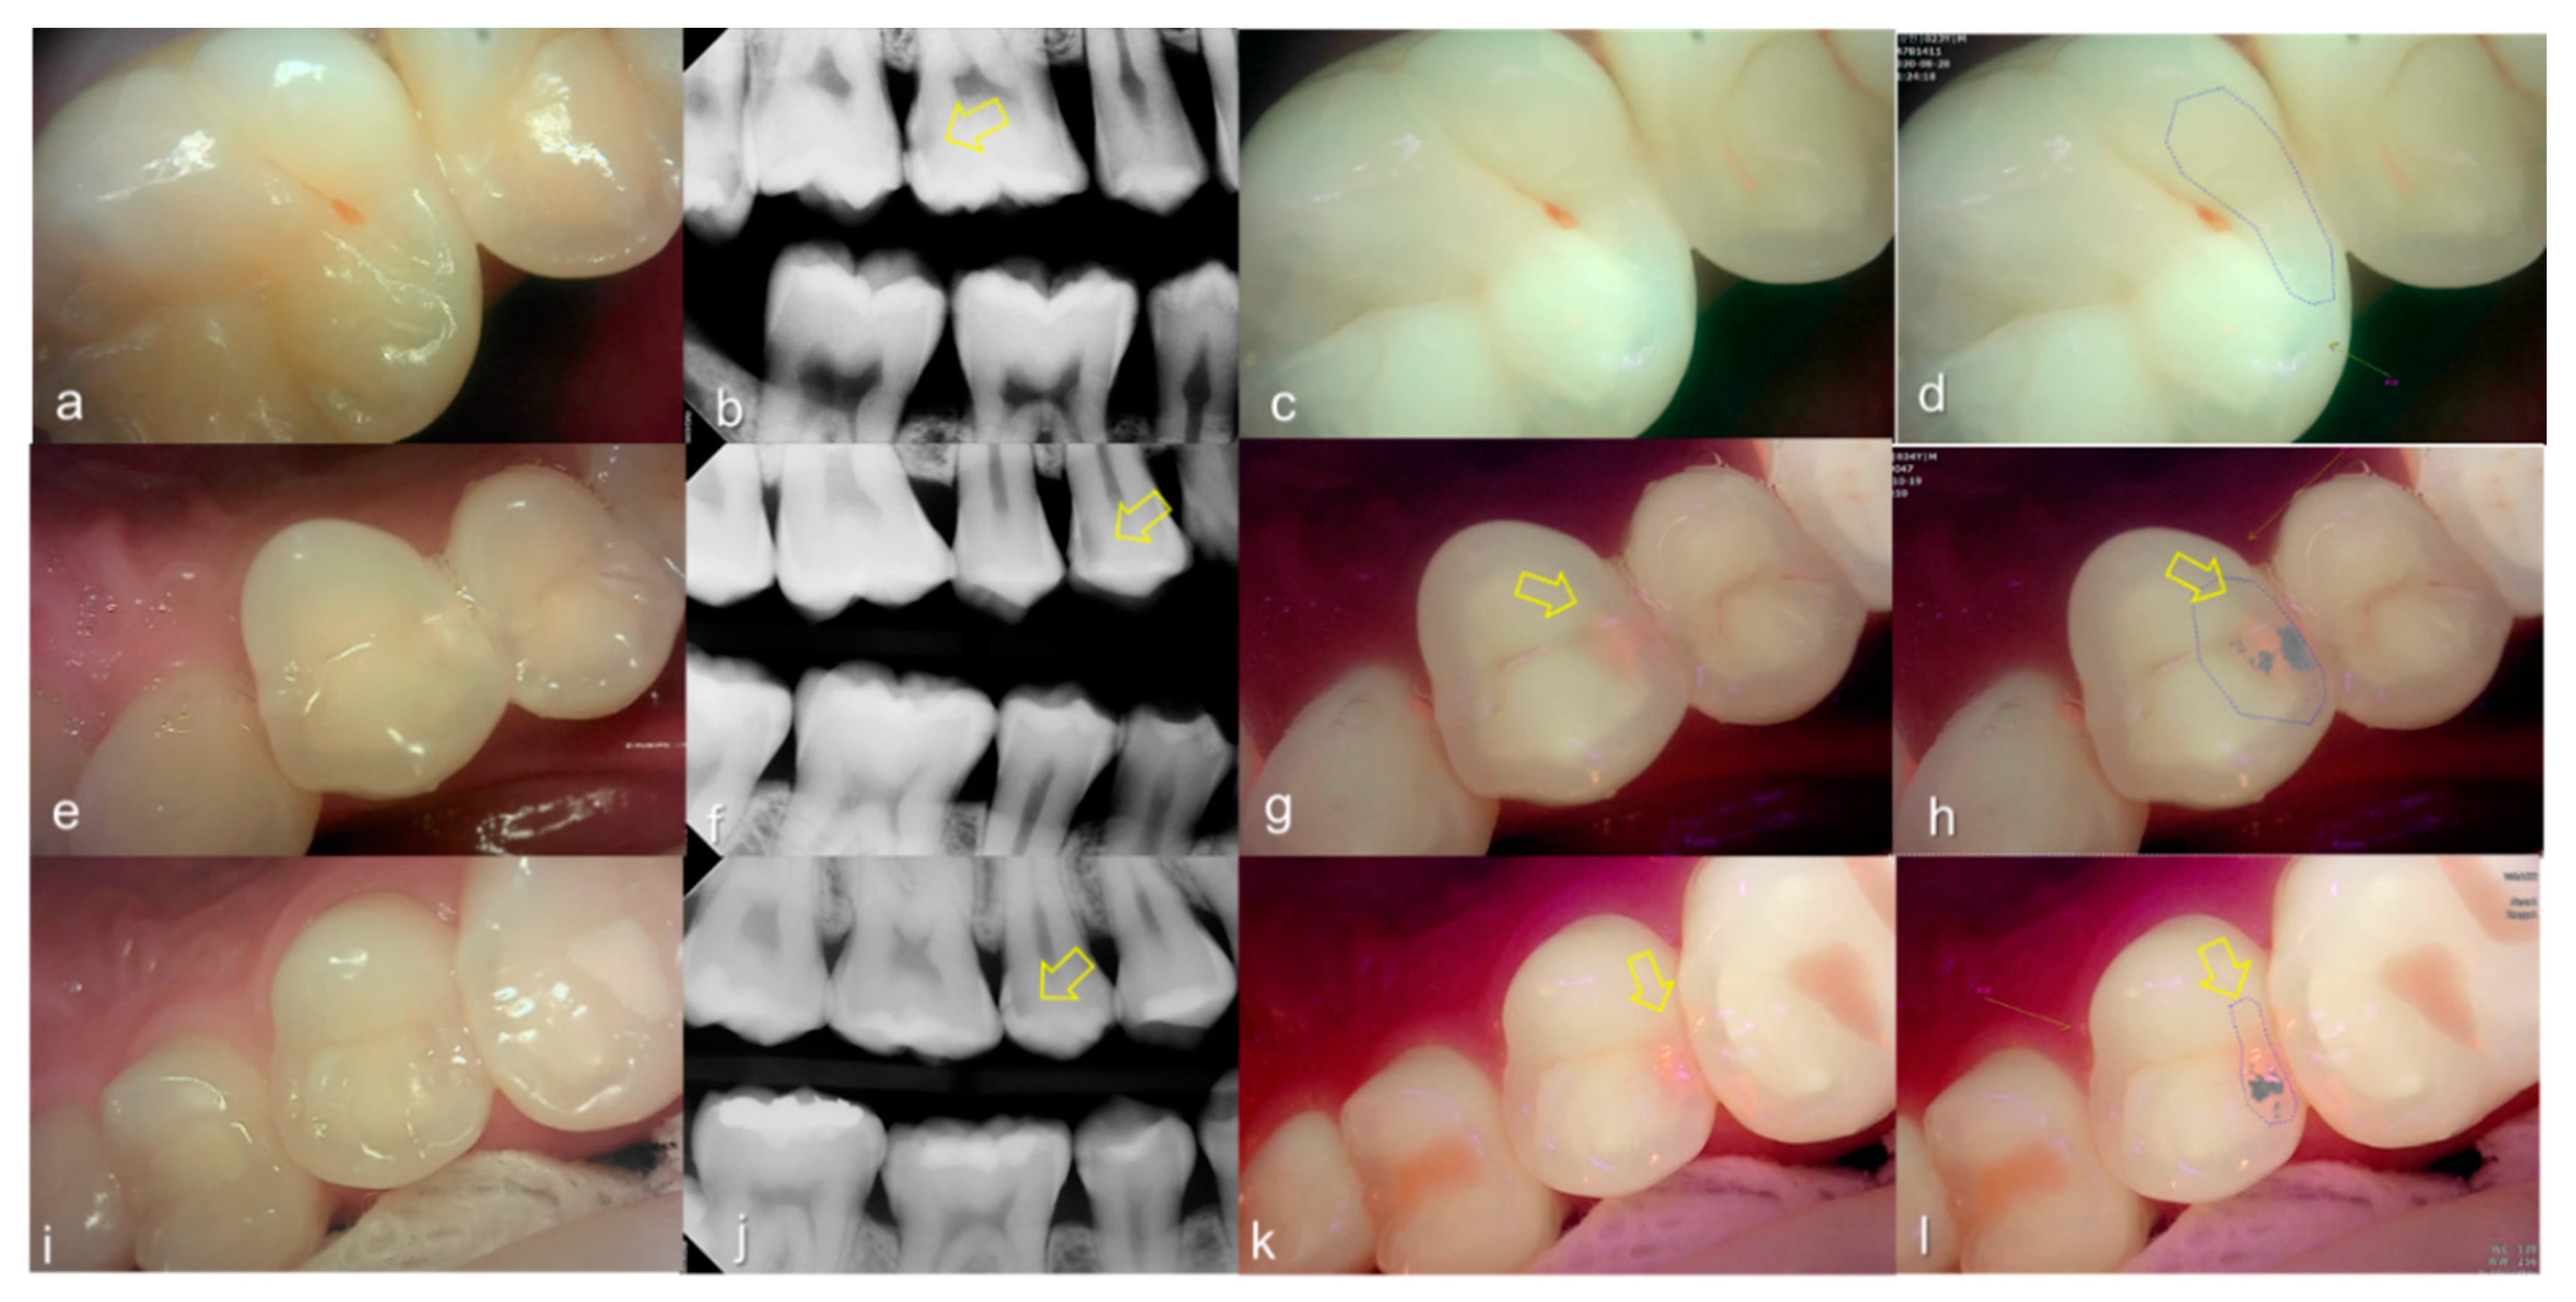

Evaluating proximal dental caries according to the QLF criteria and X-ray criteria, moderate positive correlation was observed (r = 0.63, p < 0.0001). Among the QLF parameters classified based on X-ray criteria, the |ΔFmax| value increased significantly as the score value increased from 1 to 4 (from 3.12 to 19.56). In particular, |ΔFmax| was about 5.7-fold higher for proximal dental caries score = 3 (17.64) than proximal dental caries score = 0 (3.12), and the maximum loss of fluorescence was 6.3-fold higher for the proximal dental caries score = 4 (19.56) (Table 2). The cut-off value of |ΔFmax| for detecting proximal dental caries (X-ray criteria scores 0 and 1 vs 2–4) was 5.95. The sensitivity, specificity and AUROC of parameter were 0.74, 0.73 and 0.81, respectively. However, the sensitivity, specificity and AUROC of the parameter ΔRmax were 0.83, 0.00 and 0.59 (Table 3). Representative images of QLF and bitewing radiograph of proximal dental caries are shown in Figure 6, Figure 7 and Figure 8.

Figure 7.

Proximal dental caries: (a–d) QLF caries score 0 (no fluorescence loss and no red fluorescence increase in occlusal surface (distal side)) and radiographic caries score 3 (radiolucency extending to the middle 1/3 of the dentine) on #16; (e–h) QLF caries score 2 (fluorescence loss and red fluorescence glow extending around occlusal surface (distal side)) and radiographic caries score 3 (radiolucency extending to the middle 1/3 of the dentine) on #14; (i–l) QLF caries score 2 (fluorescence loss and red fluorescence glow extending around occlusal surface (distal side)) and radiographic caries score 3 (radiolucency extending to the middle 1/3 of the dentine) on #15; (a,e,i): white-light image of QLF; (b,f,j): fluorescence image of QLF; (c,g,k): bitewing radiograph; (d,h,l): analyzed QLF image using QA2 software.